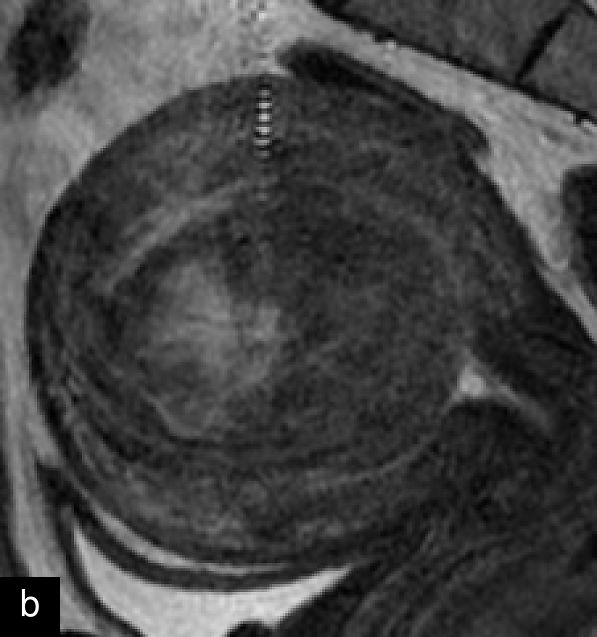

Magnetic resonance imaging (MRI) may help in the preoperative evaluation of uterine masses, when ultrasound findings are inconclusive. MRI offers higher accuracy in soft-tissue contrast, a larger field of view, diffusion imaging and multiplanar capabilities.15 A recent consensus statement has provided a standardized approach to MRI assessment, emphasizing its role in distinguishing uterine sarcomas/STUMP from benign leiomyomas.15 Features suggestive of malignancy include irregular margins; heterogeneous and high signal on T2 weighted imaging; and hemorrhagic and necrotic changes, with central non-enhancement, hyperintensity on diffusion-weighted imaging (DWI), and low values for apparent diffusion coefficient (ADC)15,25,39,40,41 (Figure 7). Diagnostic algorithms have been proposed to support MRI interpretation in differentiating between benign and malignant uterine lesions, and recent studies have explored the use of artificial intelligence to further enhance diagnostic accuracy.42,43,44 Emerging technologies, including radiomics and machine learning, show promise in improving diagnostic precision, although standardization and external validation remain essential.39,45

7

Magnetic resonance imaging (MRI) of a STUMP. (a) Contrast-enhanced MRI showing heterogeneous enhancement of the mass. (b) T2-weighted MRI demonstrating a hyperintense lesion with heterogeneous signal intensity. (c) Diffusion-weighted imaging (DWI) highlighting areas of restricted diffusion. (d) Apparent diffusion coefficient (ADC) map, showing low ADC values suggestive of increased cellularity, aiding in the differentiation of STUMP from benign leiomyomas and malignant leiomyosarcomas.